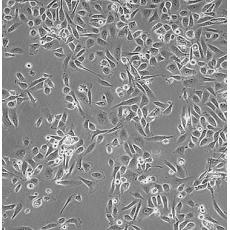

PC-3M

產品名稱 PC-3M

中文名稱 人前列腺癌細胞

組織來源 前列腺癌;骨髓轉移;男性

生長特性 adherent

培養基 RPMI-1640+10% FBS+1% P/S

形態特征 epithelial

傳代方法 1:2-1:4